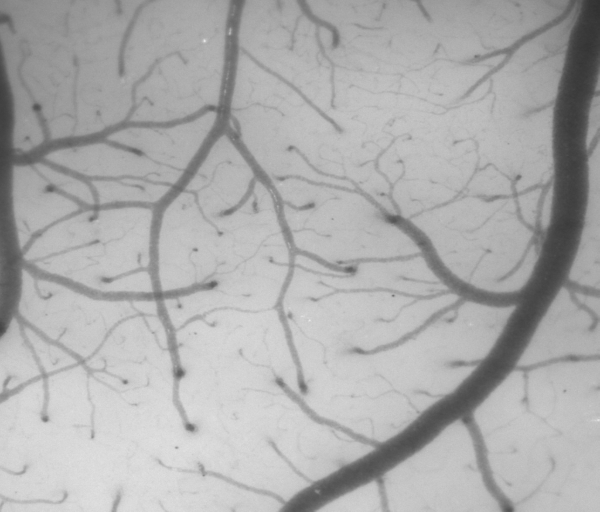

本文我们使用一张光照不均匀的血管图像来检验所实现算法的效果,如下图所示,可以看到原本图像的光照信息就是不均匀的,所以计算出来的背景图像上不同区域的明暗并不一样。

原图

背景图